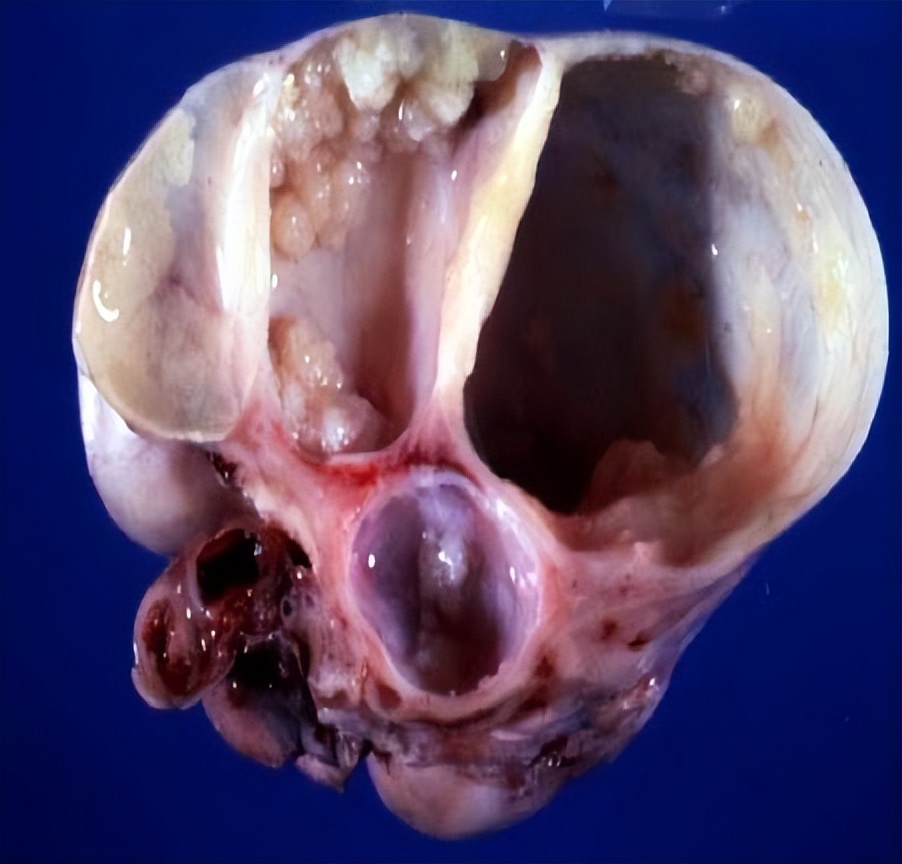

03、 卵巢畸胎瘤

这是一种病理性囊肿,好在一般是良性的。卵巢畸胎瘤由胚胎来源的细胞形成,可包含人体的各种成分,如头发、骨成分或脂质。

05、 卵巢子宫内膜异位囊肿

俗称“巧克力囊肿”,它跟巧克力没啥关系,是因为囊内咖啡色液体粘稠似巧克力而得名。当子宫内膜细胞异位生长到卵巢,随月经周期性出血就会形成“巧克力囊肿”。